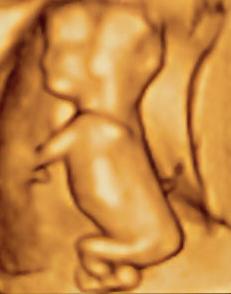

산부인과 초음파는 태아의 크기로 임신 주수를 측정하고, 태아의 수와 태반을 확인하며, 자궁외 임신과 임신 초기 출혈을 평가하는 데 일상적으로 사용된다. 태아의 성장이 다른 요인에 의해 크게 영향을 받기 전인 임신 초기, 특히 첫 번째 삼분기에 가장 정확하게 측정된다.[22] 초음파는 또한 선천적 기형(또는 기타 태아 기형)을 감지하고 생물리학적 프로파일 (BPP)을 결정하는 데 사용되며, 태아 구조가 더 크고 발달된 임신 두 번째 삼분기에 일반적으로 더 쉽게 감지할 수 있다.[23]

X-선 및 전산화 단층 촬영 (CT)은 특히 임신 초기에는 이온화 방사선으로 인해 사용되지 않으며, 이는 태아에게 기형 발생 효과가 있다.[24] 자기 공명 영상 (MRI)이 태아에게 미치는 영향은 입증되지 않았지만,[25] 이 기술은 일상적인 관찰에는 너무 비싸다. 대신, 산부인과 초음파는 방사선을 방출하지 않고 휴대 가능하며 실시간 영상을 허용하므로 임신 초기 및 임신 기간 동안 선택되는 영상 방법이다.[26]

잦은 초음파 검사의 안전성은 확인되지 않았다. 그럼에도 불구하고, 성별 스캔, 3D 및 4D 스캔과 같이 의료적 목적 없이 추가 스캔을 선택하는 여성의 수가 증가하고 있다.[27] 정상적인 임신에서는 임신 낭, 난황 낭, 태아 극이 나타난다.[28]